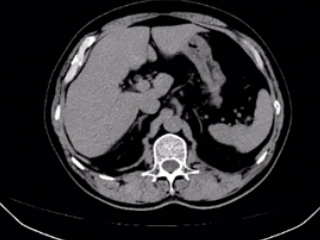

▲术前